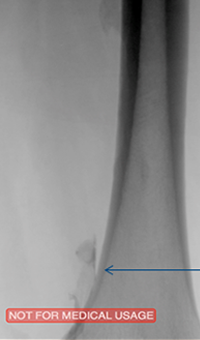

Thrombectomy of occluded SFA

Thrombectomy of Occluded SFA - pre-procedure

Imaging SFA showing thrombus and calcification

Male in his late 40s presenting with pain in his right leg. An angiogram showed a total occlusion in the right superior femoral artery (SFA)

Thrombectomy of Occluded SFA - catheter positioning

Solent™ Proxi catheter positioned before the lesion

The physician delivered (antegrade) the Solent Proxi catheter to the proximal margin of the occlusion

Thrombectomy of Occluded SFA - thrombus removed

Thrombus removed following AngioJet™ treatment

After the third pass with Solent Proxi

Thrombectomy of Occluded SFA - post-adjunctive treatment

Post-adjunctive treatment

Final angiogram showing flow post-treatment

Results from case studies are not necessarily predictive of results in other cases. Results in other cases may vary.